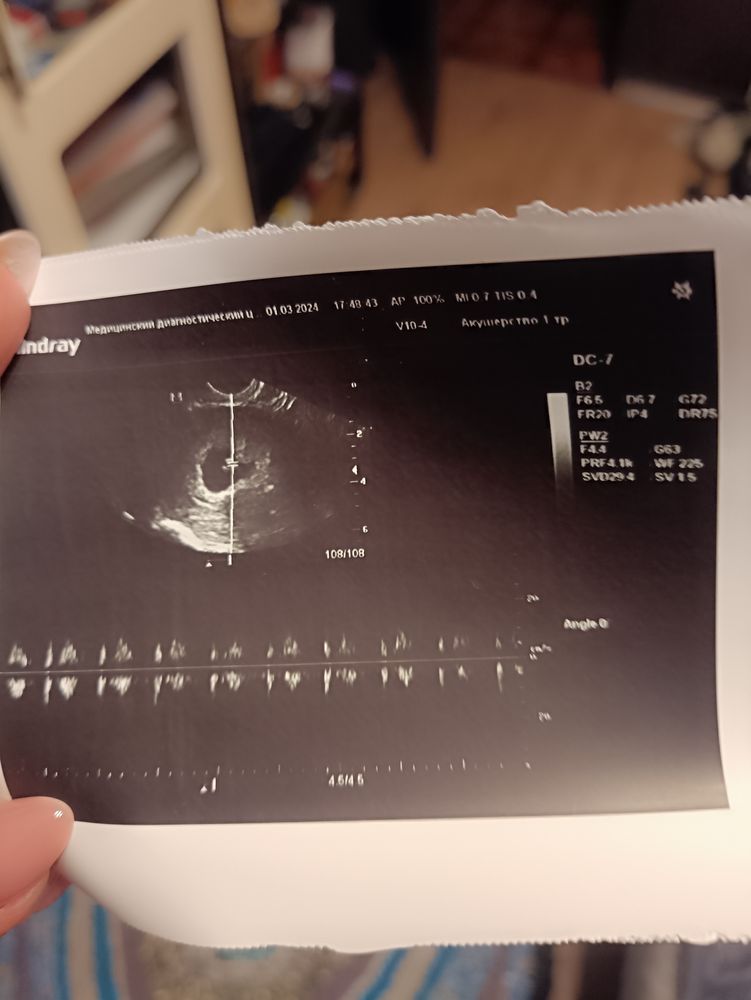

Все есть) я самая счастливая) СБ+ слушала его и плакала) чсс 152

Увидела эмбриончик, ктр соответствует 6 нед 6 дней, что соответствует сроку.